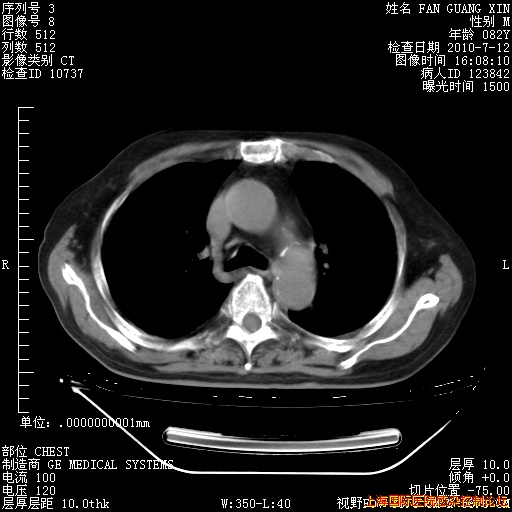

6月12日纵膈窗